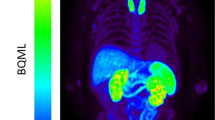

Further development of folate imaging agents also focused on PET tracers, which could be used for detection of (sub)clinical arthritis as well as for more accurate therapy monitoring. To this end, a folate PET tracer, [18F]-fluoro-PEG-folate, was synthesized in a two-step procedure and evaluated in an antigen-induced arthritis model in rats [48]. Uptake of [18F]-fluoro-PEG-folate was significantly higher in arthritic than in non-inflamed control knees, and also arthritic knee to bone and arthritic knee to blood ratios were higher for [18F]-fluoro-PEG-folate than (R)-[11C]PK11195 [48]. In addition, using [18F]-fluoro-PEG-folate PET, it was possible to monitor therapeutic effects of MTX in arthritic rats [49] and to monitor systemic inflammatory effects in an arthritic rat model [50]. Based on these encouraging preclinical results, [18F]-fluoro-PEG-folate was taken to a clinical setting in which this tracer could readily visualize arthritic joints in RA patients [130]. Recently, a novel folate-based PET tracer was synthesized in a faster (< 1 h) one-step procedure, i.e., [18F]-folate-PEG-NOTA-Al [131], which warrants further (pre)clinical evaluation.